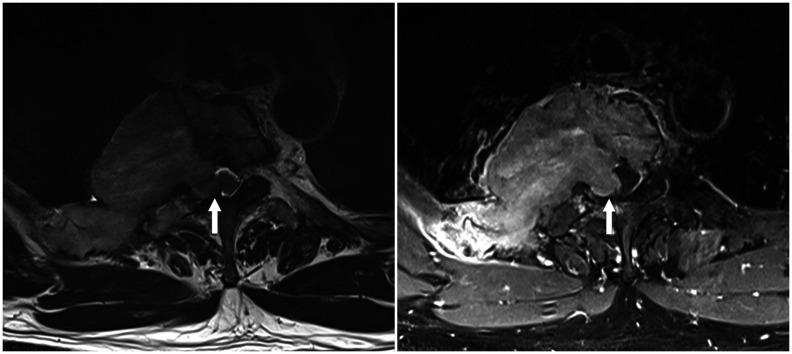

Magnetic resonance imaging (MRI) has become a crucial tool for evaluating mediastinal masses considering that several lesions that appear indeterminate on computed tomography and radiography can be differentiated on MRI. Using a three-compartment model to localize the mass and employing a basic knowledge of MRI, radiologists can easily diagnose mediastinal masses. Here, we review the use of MRI in evaluating mediastinal masses and present the images of various mediastinal masses categorized using the International Thymic Malignancy Interest Group's three-compartment classification system. These masses include thymic hyperplasia, thymic cyst, pericardial cyst, thymoma, mediastinal hemangioma, lymphoma, mature teratoma, bronchogenic cyst, esophageal duplication cyst, mediastinal thyroid carcinoma originating from ectopic thyroid tissue, mediastinal liposarcoma, mediastinal pancreatic pseudocyst, neurogenic tumor, meningocele, and plasmacytoma.

磁共振成像(MRI)已成为评估纵隔肿块的重要工具,因为 CT 和 X 线摄影上表现为不确定的一些病变可以在 MRI 上区分。使用三室模型定位肿块并运用 MRI 的基本知识,放射科医生可以轻松诊断纵隔肿块。在这里,我们回顾了 MRI 在评估纵隔肿块中的应用,并展示了使用国际胸内恶性肿瘤兴趣小组的三室分类系统对各种纵隔肿块进行分类的图像。这些肿块包括胸腺增生、胸腺囊肿、心包囊肿、胸腺瘤、纵隔血管瘤、淋巴瘤、成熟畸胎瘤、支气管囊肿、食管重复囊肿、起源于异位甲状腺组织的纵隔甲状腺癌、纵隔脂肪肉瘤、纵隔胰腺假性囊肿、神经源性肿瘤、脑脊膜膨出和浆细胞瘤。